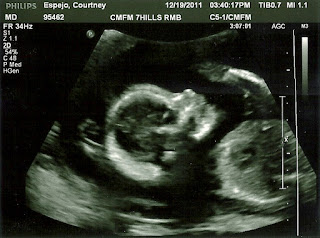

...we had another ultrasound for the new baby. The doc said her heart looks great and since everything is going so perfect, we won't have another ultrasound until March. Although I'll miss watching her bounce around in my belly, I can now feel her and see her tiny movements underneath my skin, so the fact that she's perfectly healthy and doesn't need any monitoring is a plus in my book. I did get a pretty good profile picture of her this time. I think she looks a lot like Grace! Here's a comparison: BABY #2: GRACE: I know you're probably thinking that most ultrasound pictures look alike, but I've got tons of friends that are pregnant right now or just had babies, and you can definitely tell the difference. These babies have the same nose, chin, and mouth. I may be biased, but I think Grace is the cutest little girl I've ever seen, so I'm really hoping that this new baby looks exactly like her! ...Noah came over to play and he and Grace roc...